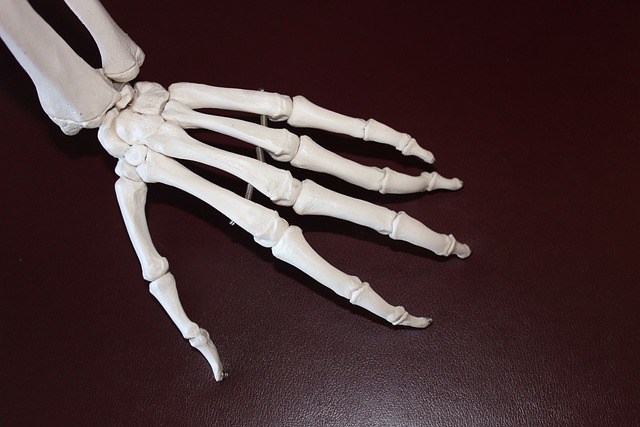

나이가 들거나 과도한 운동, 비만 등으로 인해 관절 통증을 겪는 사람들이 많습니다.

관절 건강을 유지하려면 충분한 영양소를 섭취하고 생활 습관을 개선하는 것이 중요합니다.

특히 글루코사민, 콘드로이틴, 오메가-3, 칼슘, 비타민D 등은 연골 보호와 염증 완화에 도움을 주는 필수 영양소입니다.